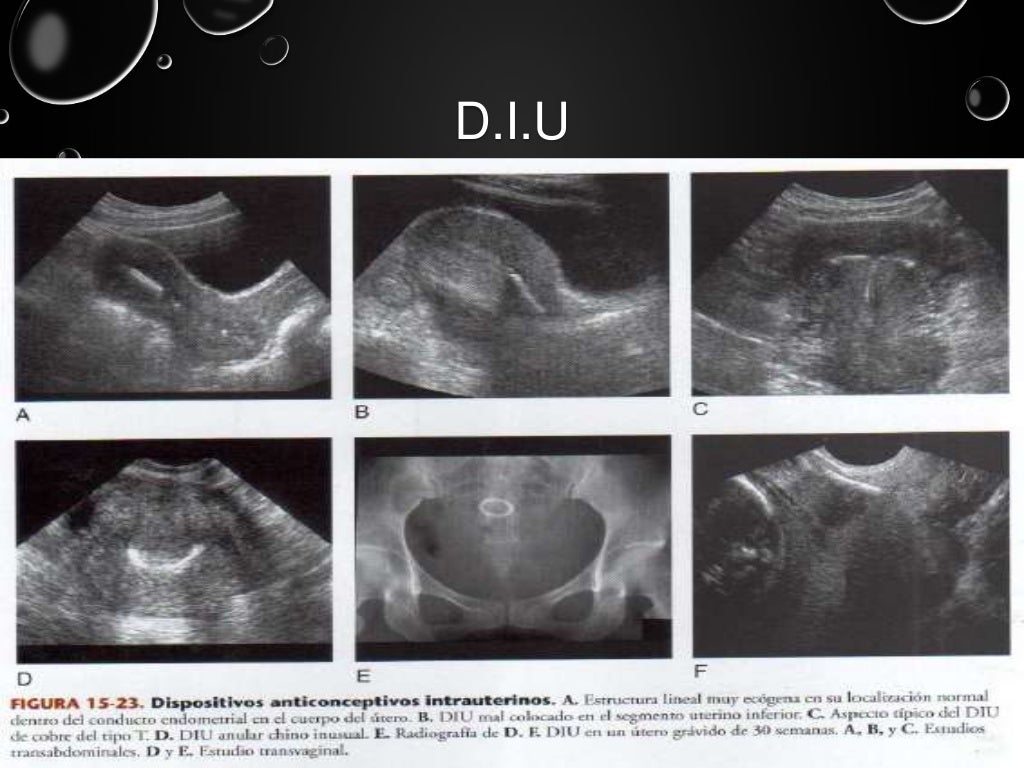

Ultrasonido pelvico

Source: es.slideshare.net